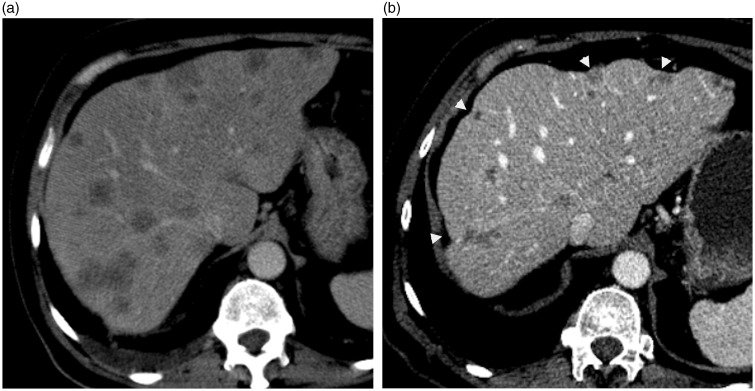

Hepatic capsular retraction is an imaging feature that deserves the attention of the radiologist. Hepatic capsular retraction is associated with a number of hepatic lesions, benign or malignant, treated or untreated. The purpose of this pictorial review is to discuss the most common benign and malignant hepatic lesions associated with this feature with an emphasis on magnetic resonance imaging (MRI).